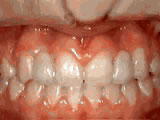

Open Bite Correction

Started treatment at age 13 with braces and a tongue-training crib appliance for 28 months to correct an open bite caused by thumb-sucking — now enjoys a normal bite.

Open bite - Front teeth don't touch Before Open bite - Front teeth don't touch after